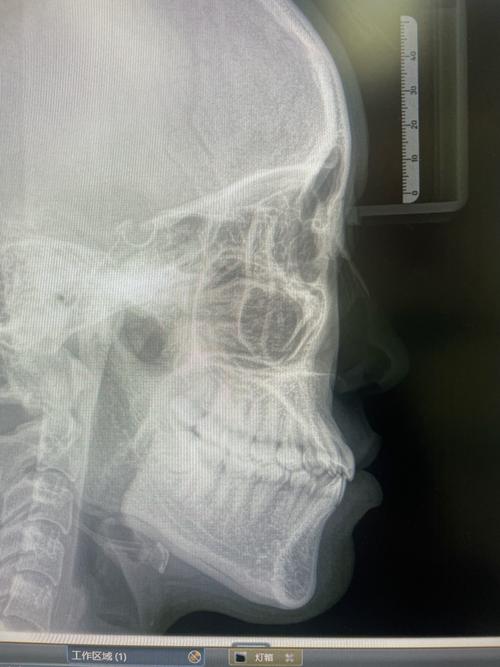

- 颌骨关系判断错误: 在头颅侧位片中,上下颌骨的前后、垂直关系(如ANB角、颌平面角等)是诊断骨性错颌畸形的关键指标,角度过大(尤其是侧位片时头部旋转或仰俯角度不对)会严重扭曲这些角度,导致对骨骼问题的误判(比如把骨性错判成牙性错,或反之)。

- 关节位置偏移: 在评估颞下颌关节时,角度偏差可能导致关节窝、髁突位置显示不清或位置异常,影响对关节健康或紊乱的判断。

- 漏诊或误诊: 基于失真的影像,医生可能无法准确识别某些问题,例如埋伏牙的位置、阻生牙的方向、骨量不足的程度、牙根吸收情况、牙根位置异常(如靠近下颌管)等。